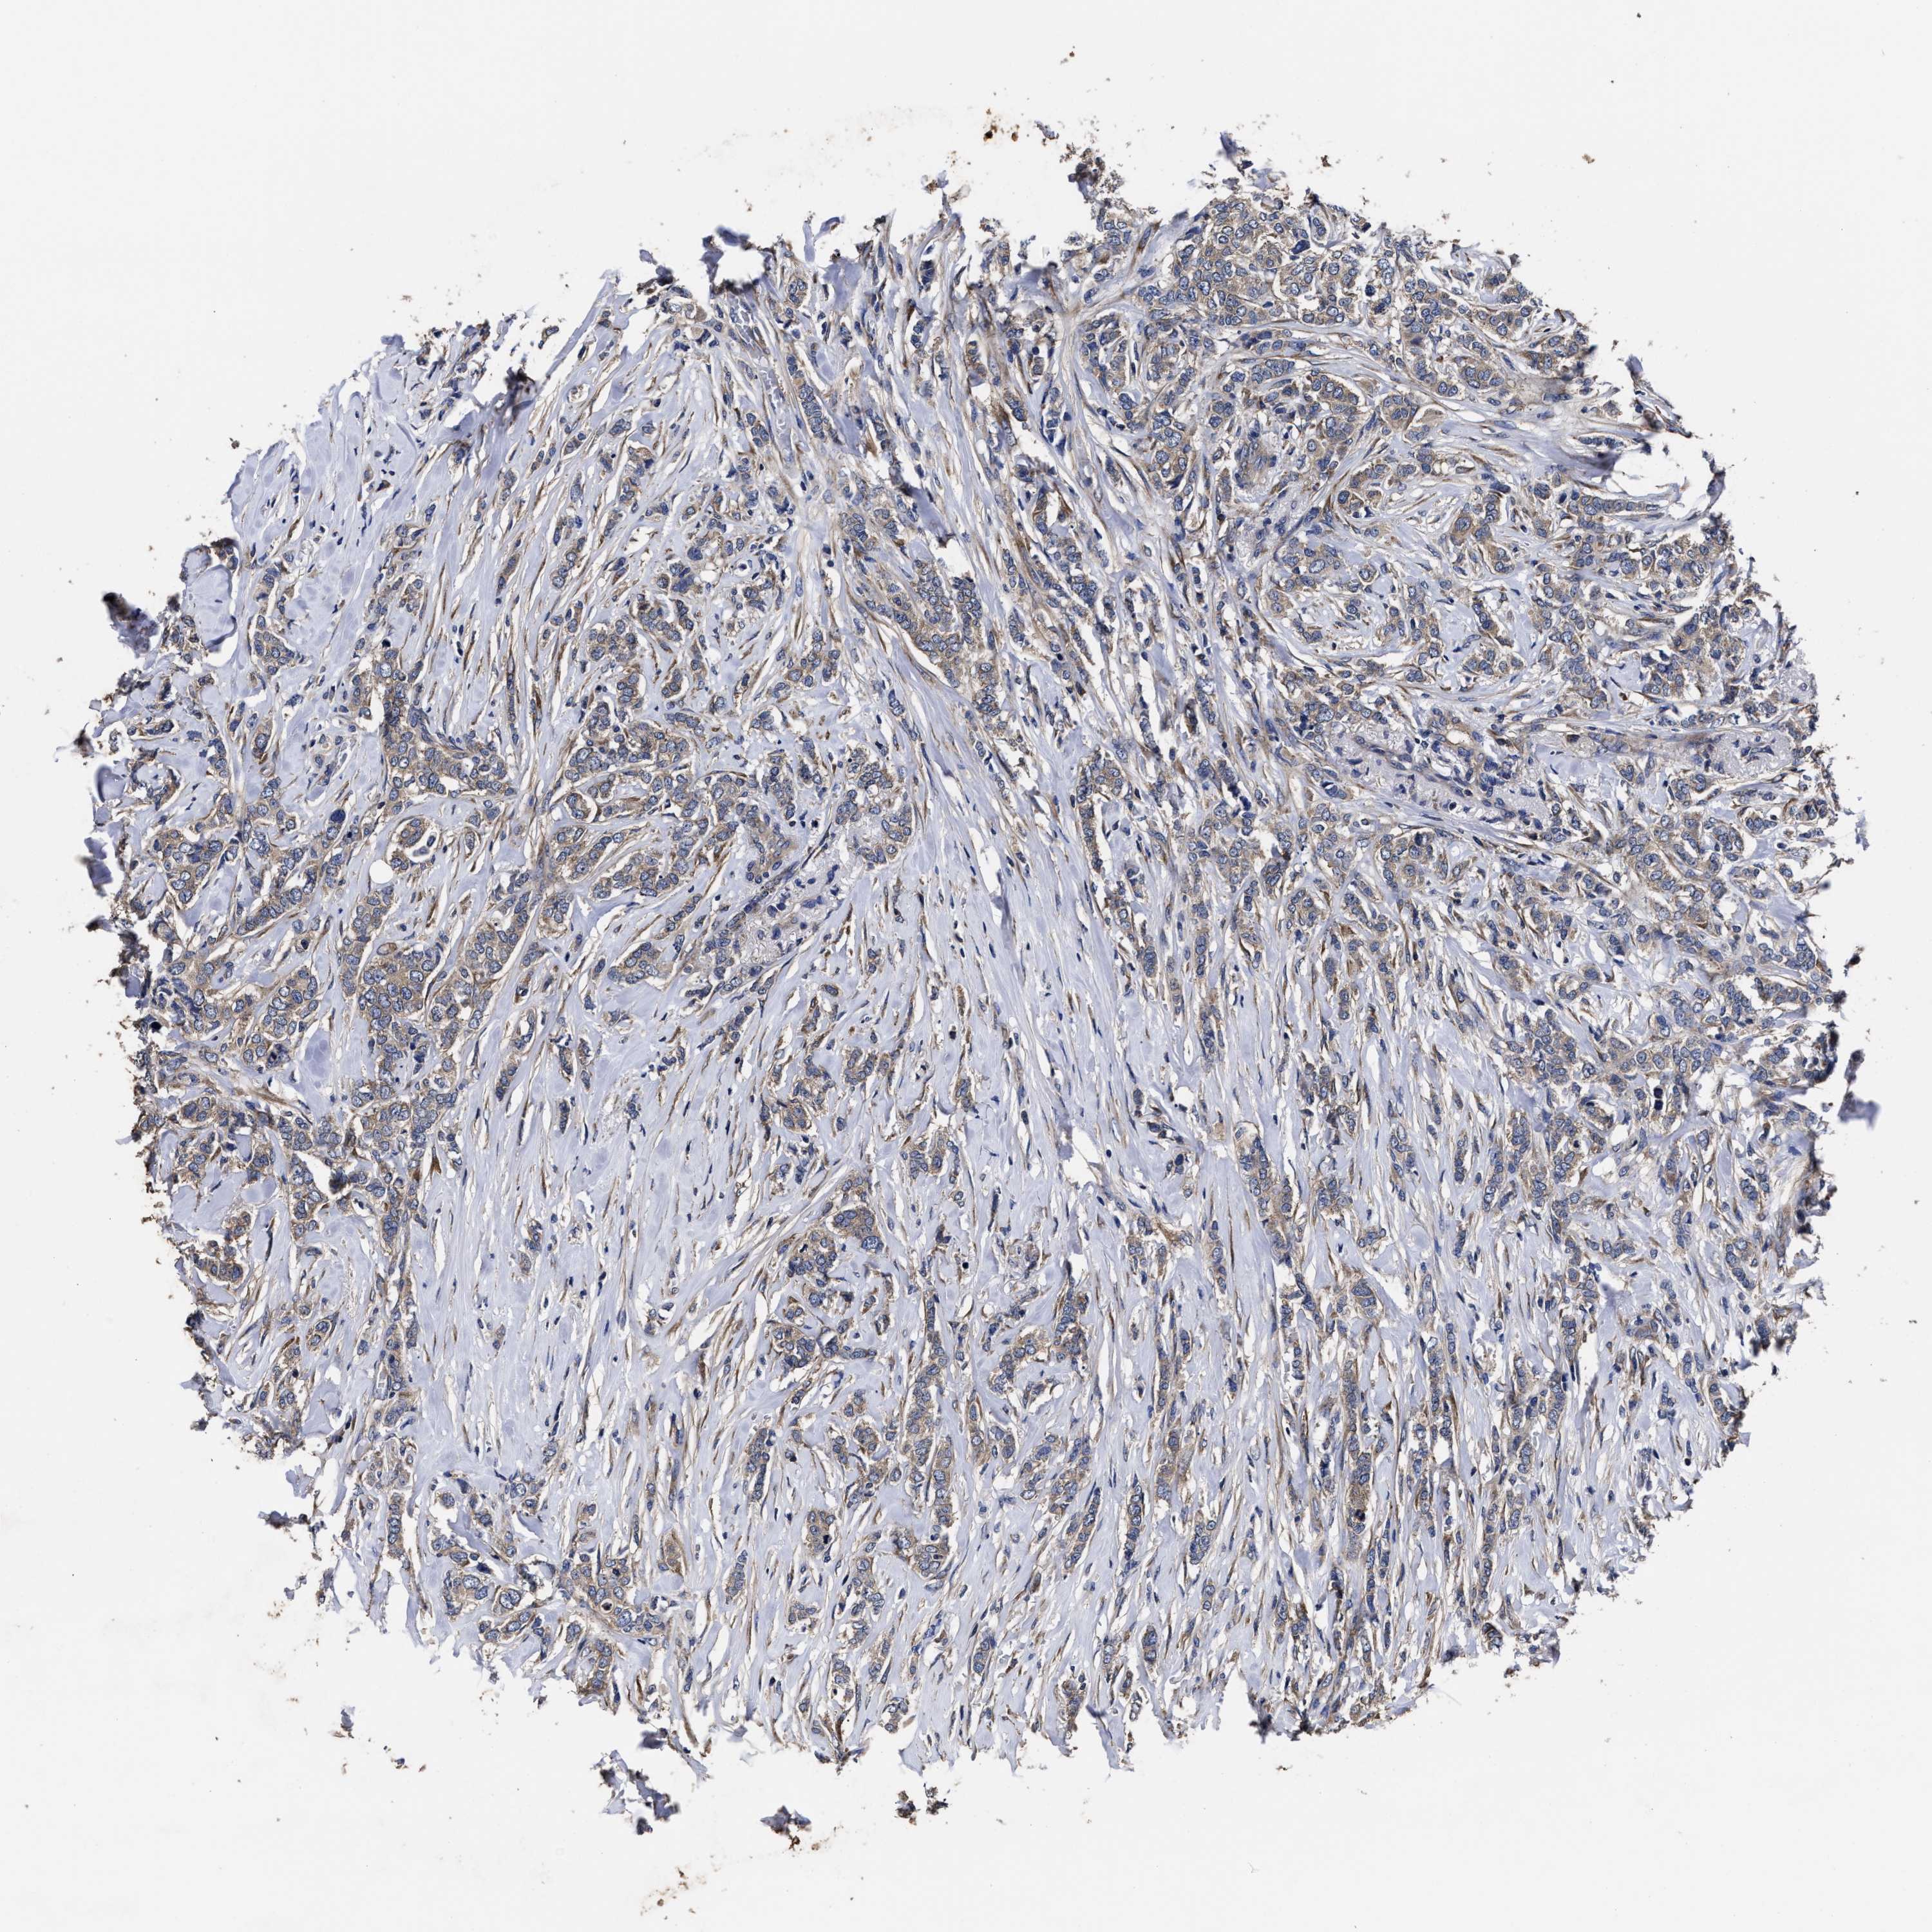

CANCER BREAST CANCER Show tissue menu

BRCA TCGA BRCA VALIDATION PROTEIN EXPRESSION